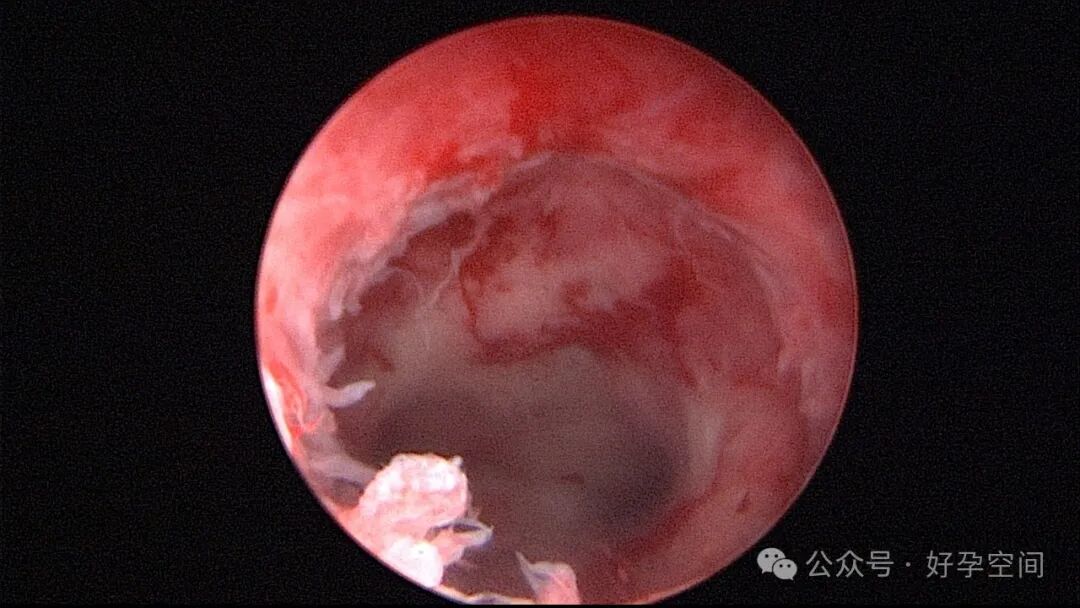

患者24岁,G6P3,顺产1次,双胎剖宫产1次。本次停经53天,计划外妊娠,行宫腔镜取胚及安环术。摘除胚胎后见宫腔右侧壁胚胎附着部位包块,约1.0cm*1.0cm*0.8cm,宫腔镜切除包块送病检,放置γ环一个,环两臂卷曲于右侧宫角,宫腔镜钩住环尾部下拉,上推节育环右臂,将环调整到正常位置。术后病检结果为“宫腔胎盘附着部位超常反应”。

超常胎盘部位(exaggerated placental site,EPS)反应是指在胎盘附着部位组织的过度反应性病变。1991年,WHO将其列入滋养细胞疾病,但目前国内外对该病的诊断尚无统一标准。在正常妊娠中,中间型滋养细胞可侵入底蜕膜或浅肌层,而超常胎盘部位反应时,中间型滋养细胞在胎盘部位大量浸润,并侵入子宫肌层,是正常胎盘反应的加剧,是一种滋养细胞疾病。EPS反应可发生于正常妊娠、流产或葡萄胎后,发生于葡萄胎者浸润力更为明显。EPS以病理诊断为依据,其组织学特征以中间型滋养细胞为主,由子宫内膜向肌层的良性漫润,不破坏原有组织结构,伴有淋巴细胞灶性浸润。EPS是一种非肿瘤性的良性滋养细胞疾病,普通人工流产、宫腔镜取胚或产后出血增多,手术医生主观感觉宫腔已经清理干净,但B超提示宫内占位包块,应考虑到是否存在EPS,建议做宫腔镜探查,切除包块送病检,以明确诊断,避免遗漏其他严重疾病,EPS对症治疗即可,观察病情变化,预后良好。